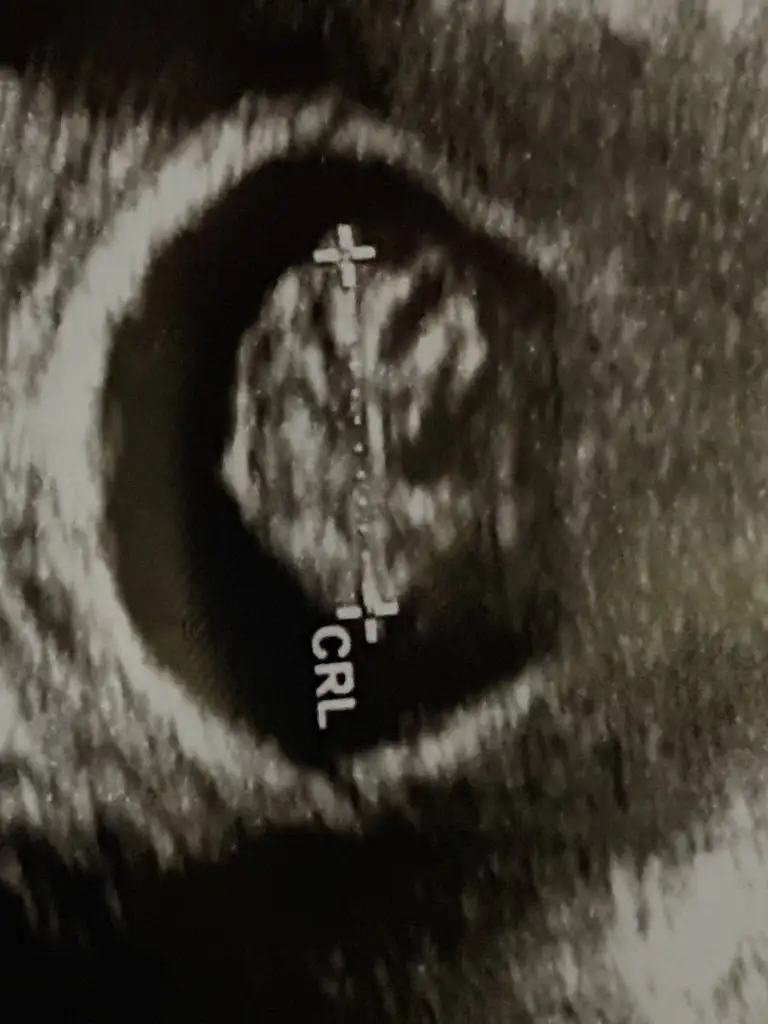

Merhaba kaç haftalık?Bu da siyah beyaz ultrason görüntüsü, erkek olduğunu gördük, fikir olsun diye paylaştım

10+3 müş ama ultrasonda önde gidiyo 11 haftalıkmışMerhaba kaç haftalık?

10+3 müş ama ultrasonda önde gidiyo 11 haftalıkmış